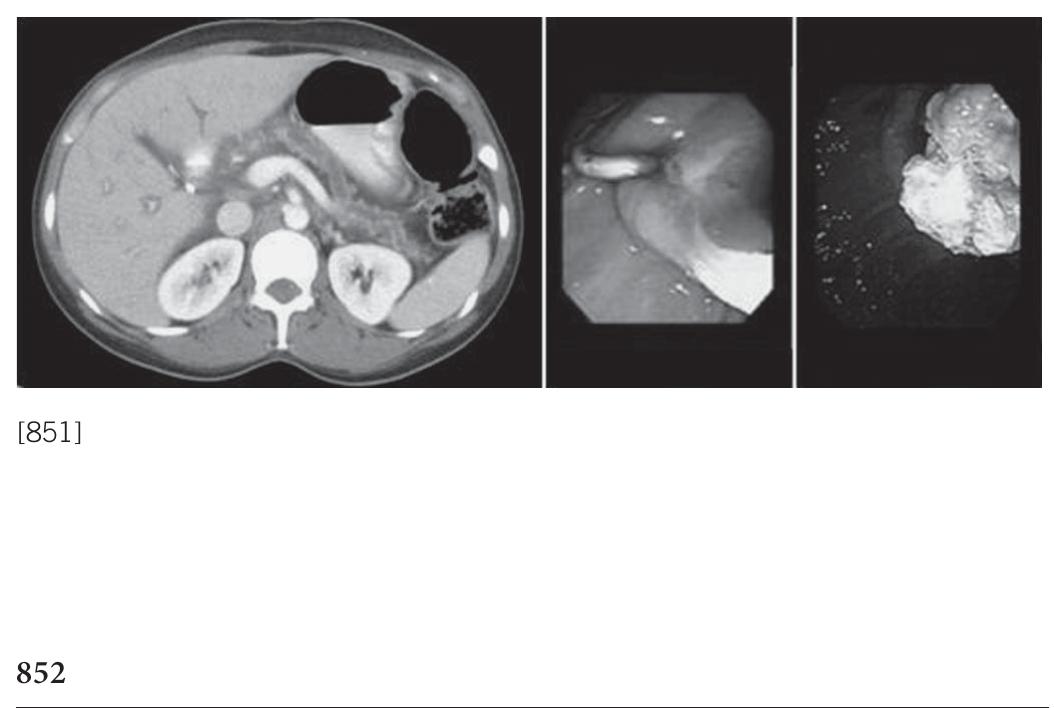

![[850] Fluoroscopic image showing proximal CBD stricture; endoscopic image showing SEMS.](https://figures.academia-assets.com/72315061/figure_123.jpg)